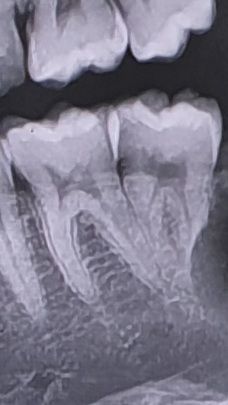

함치성 낭종 때문에 어금니 뿌리 일부분이 흡수되었습니다 파노라마상 흡수가 많이 된 것인지 궁금합니다

비교를 위해 흡수 전 파노라마도 올려봅니다

• 1번 째 사진